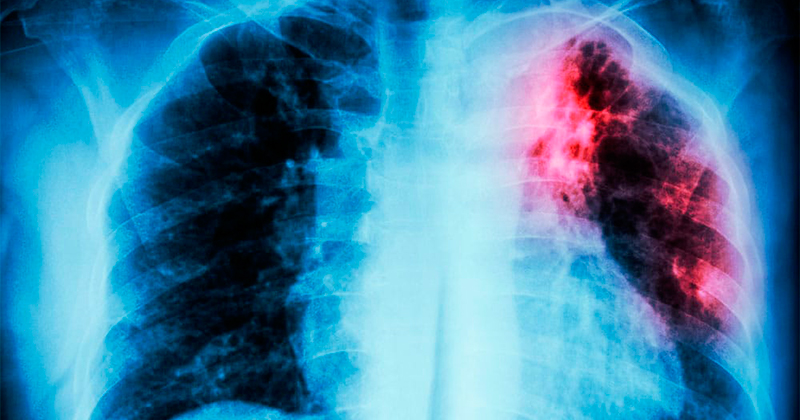

La tuberculosis, causada por la bacteria Mycobacterium tuberculosis, es una enfermedad infecciosa que afecta principalmente a los pulmones y se transmite por vía aérea.

Entre sus síntomas se encuentran tos persistente de más de tres semanas, presencia de sangre en el esputo, dolor torácico, fiebre, sudoración nocturna, pérdida de peso y fatiga.